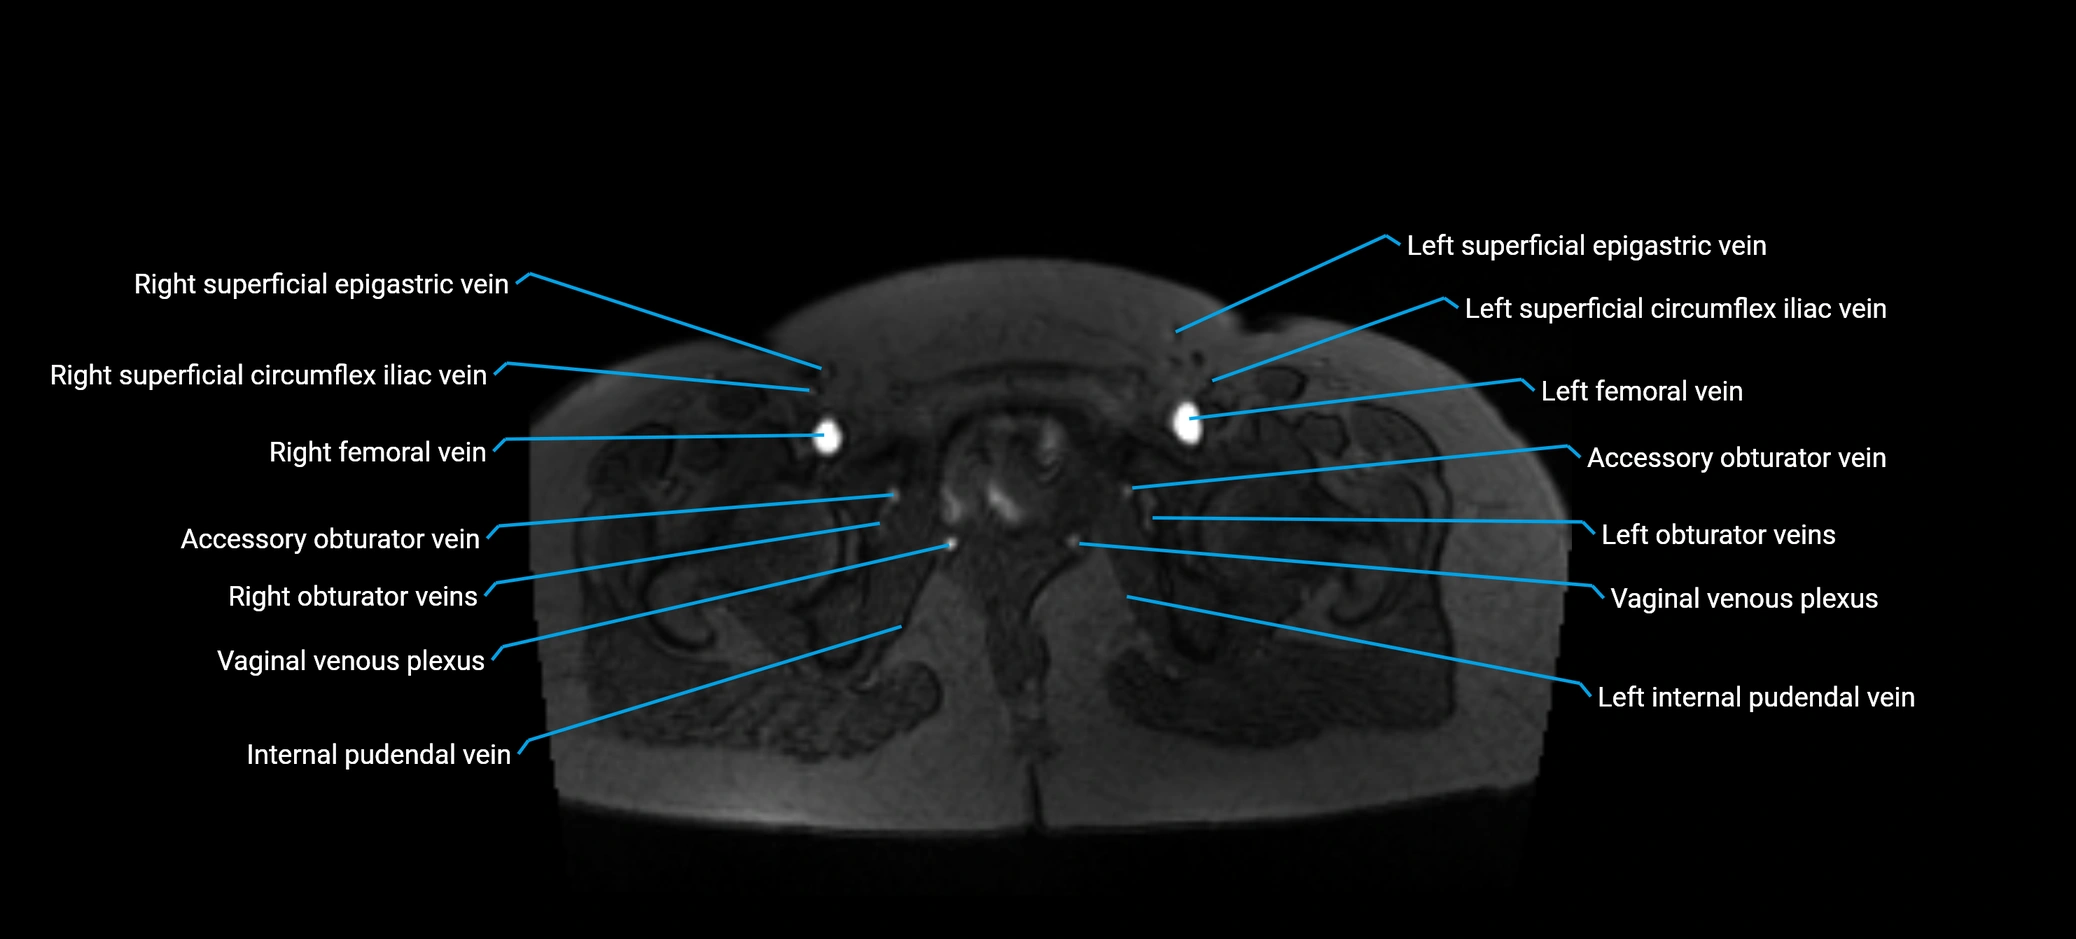

MRI image

image